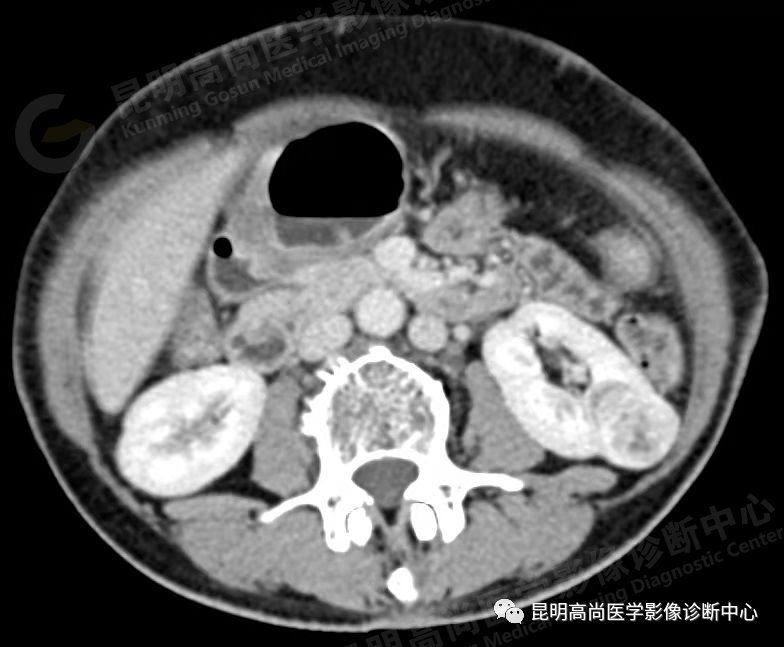

于 2021 年 9 月 17 日至本中心行 CT 平扫+增强检查;

能清晰地显示直径 1 cm 以上肾实质内肿块,肿瘤边缘不规整,呈圆形或分叶状;

平扫时,肿瘤的密度随肿瘤的细胞成分不同而略有差异,透明细胞癌的密度低于正常肾实质,而颗粒细胞癌的密度略高于正常;

增强扫描后,肿瘤密度可不同程度地增强,但仍低于正常肾组织,由于增加了肿瘤与肾组织间的密度差,可以更清楚地显示肿瘤大小与分界线;

肿瘤内常有出血、液化和坏死区,使瘤体密度变为不均性;5%-10% 肿瘤内可见密度增强的钙化灶,位于瘤体中央或边缘处;

CT 对肾细胞癌能精确估计病变的大小和范围,还可了解周围有无浸润、淋巴及远处有无转移,从而对肾癌的分期提供重要的依据。